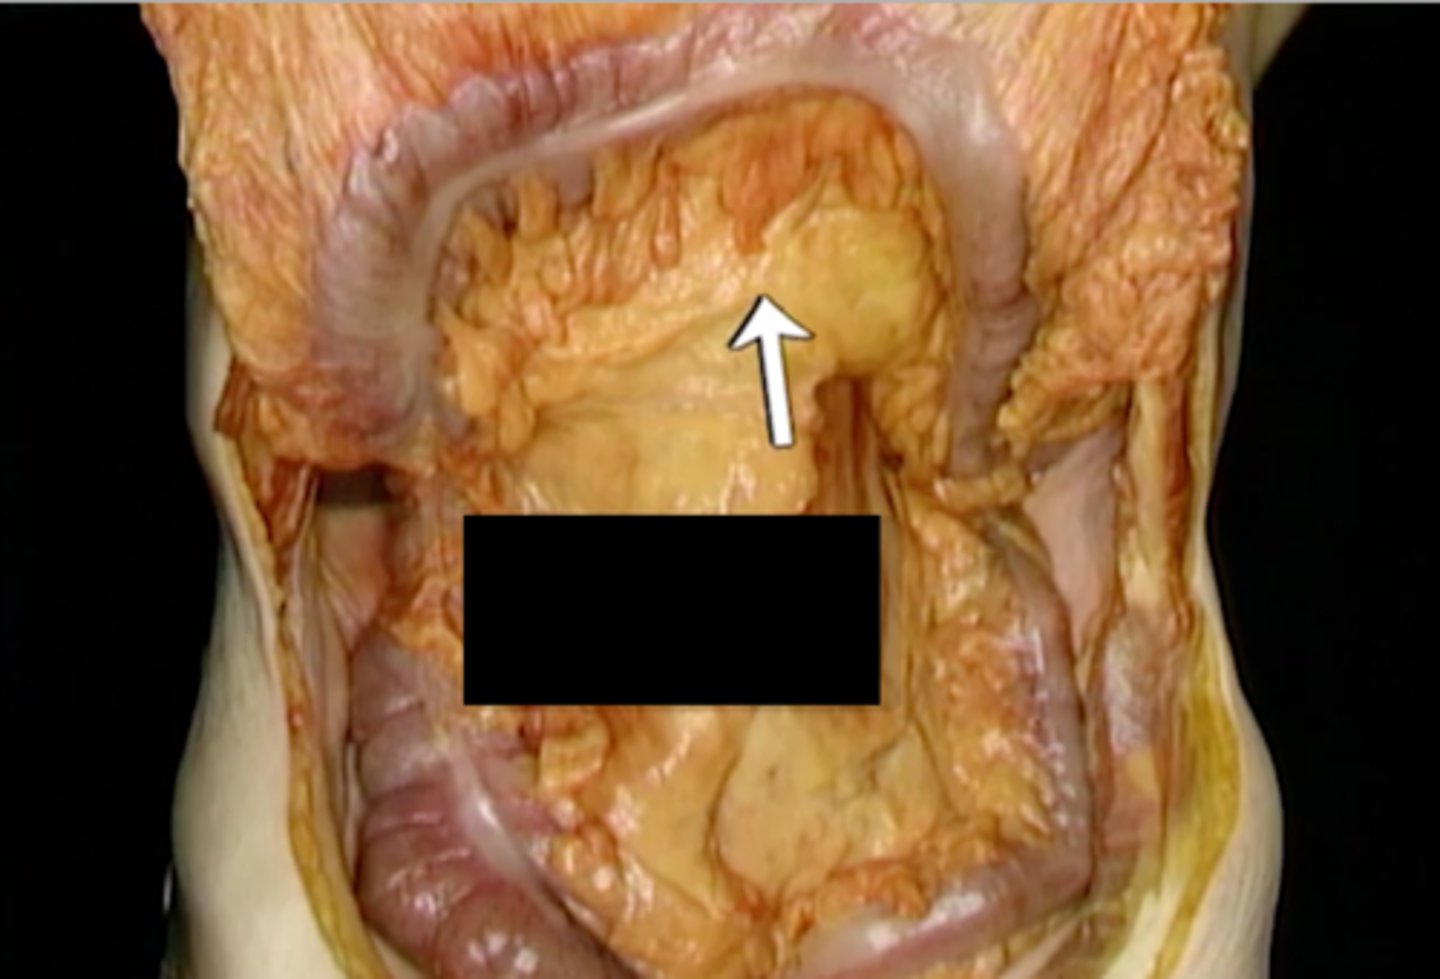

greater omentum